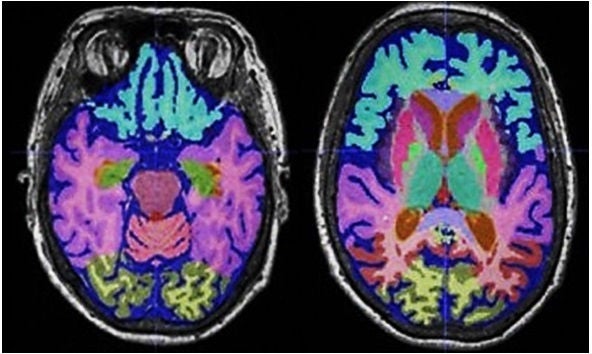

The specialists in the SGH Division of Radiological Sciences have diverse interests and expertise, and support or lead qualitative clinical and quantitative imaging research work over a wide range of imaging modalities applied to diseases of the brain, head and neck, spine, joints, breast, chest and abdomen in adults.